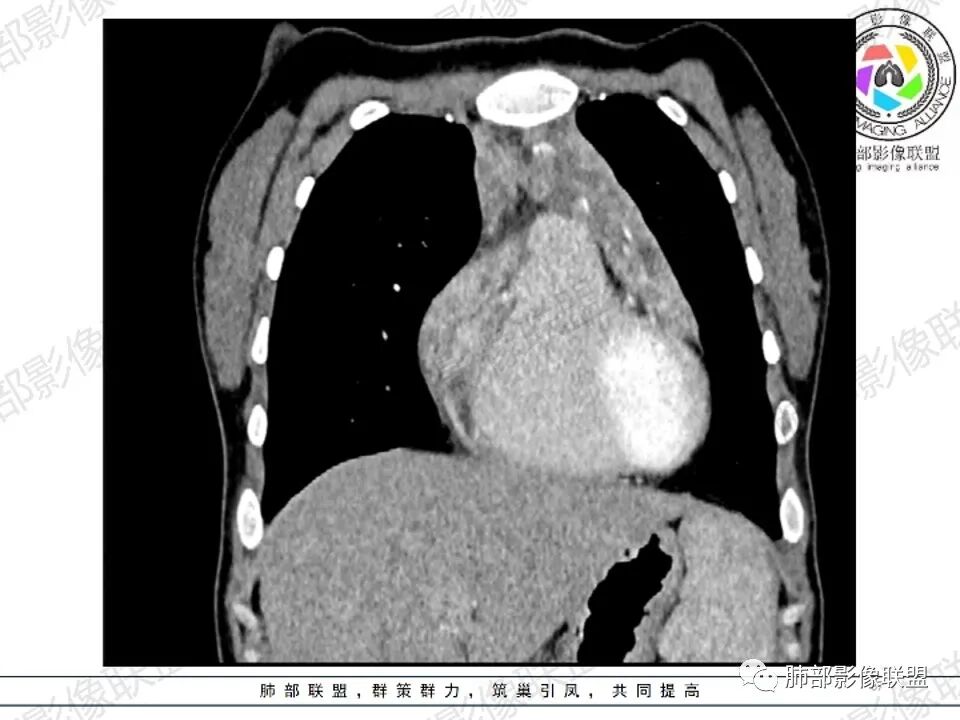

1.年轻女性,间断头晕、乏力3年,左眼视物模糊2月。门诊以贫血待查收入院。

既往曾被诊断“缺铁性贫血”“贫血所致视网膜脱离”。实验室检查资料阙如。

2.影像显示前纵隔不规则块状影,依势贴附心脏大血管旁,密度不均,边界不甚清楚,有结节融合感。

3.病灶轻度不均匀强化,可见血管穿行,散在液性低密度区。

双肺门未见肿大淋巴结。

4.双侧腋窝区见增大淋巴结,边界清楚。

关于诊断:

1.年轻女性,前纵隔不规则块状影,密度不均,边界不甚清楚,有结节融合感,轻度不均匀强化,可见血管穿行,最常见最符合的无疑是淋巴瘤!